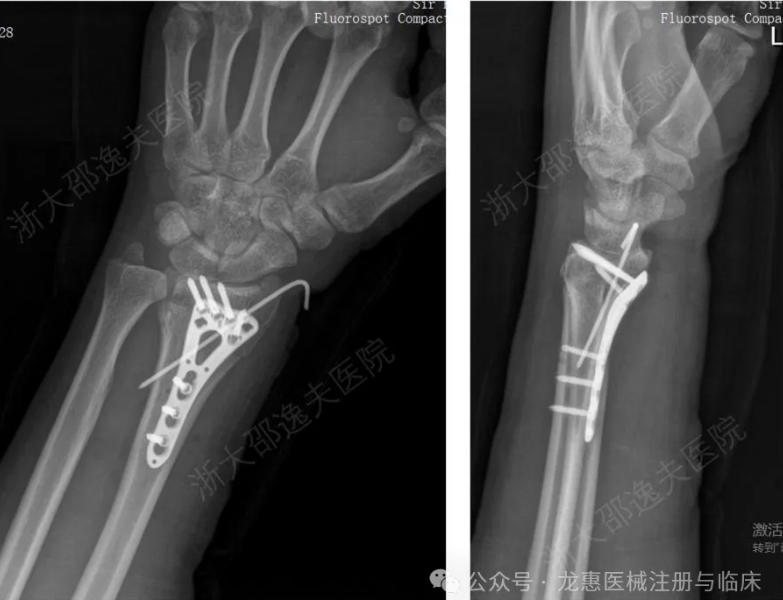

在血液浸润的湿性生理环境下实现2到3分钟即时、强效黏合; 材料可完全生物降解,约6个月后随骨愈合而自然吸收,实现真正的“无痕”,免除传统手术需二次手术之苦。 案例: 一位年轻工人因外伤导致腕部桡骨远端粉碎性骨折,传统治疗方案需大切口植入钢板螺钉,不仅创伤大、存在肌腱粘连或神经损伤风险,且需术后一年行二次手术取出。 桡骨远端骨折金属内固定治疗病例 应用“骨02”黏合技术,仅通过微创切口注入“胶水”材料,短短3分钟内即完成了粉碎骨块的精准黏合与固定。术后3个月随访显示,患者骨折愈合良好,无并发症,腕关节功能完全恢复。 桡骨远端骨折通过“骨02”治疗病例 林贤丰表示,该材料几乎适用于全身所有部位、各种尺寸的骨折修复,尤其是传统器械难以固定的微小碎骨。由于其快速黏合和使用便捷的特点,将来有望用于国防战事、灾害救援等特殊场景下的骨折紧急救治。